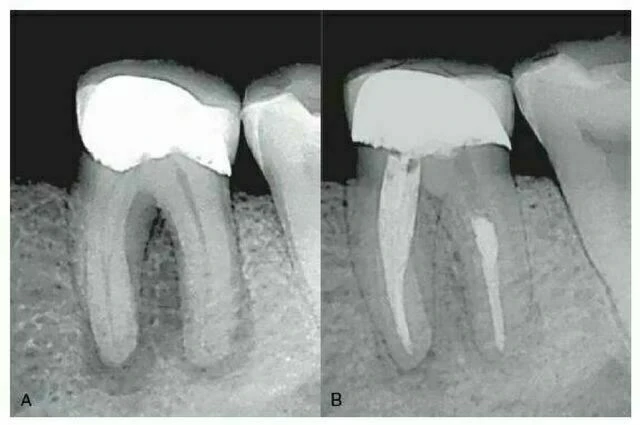

Hình 7 – 8. A, Phim trước điều trị răng cối lớn thứ nhất hàm dưới cho thấy thấu quang vùng chẽ và quanh chân răng. B, Phim sau điều trị một năm cho thấy sự lành thương đáng kể (Courtesy Dr. Raed S. Kasem, Clearwater, FL.).

Phim X-quang không đánh giá được sự hiện diện của ống tủy vùng chẽ và ống tủy bên ở chân răng. Trong một nghiên cứu cho thấy sàn tủy của 200 răng cối vĩnh viễn được nhuộm bằng fuscin 0,5%, các ống tủy vùng chẽ được thấy rõ rệt trong 24% răng cối lớn thứ nhất hàm trên và hàm dưới, 20% ở răng cối lớn thứ hai hàm dưới và 16% ở răng cối lớn thứ hai hàm trên. Các ống tủy này có thể là nguyên nhân gây ra những tổn thương nội nha chính ở vùng chẽ các răng nhiều chân (hình 7-8) và đây cũng là lý do căn bản giải thích vì sao cần đặt phục hồi gián dính ở sàn tủy nhằm ngăn ngừa việc nứt gãy.